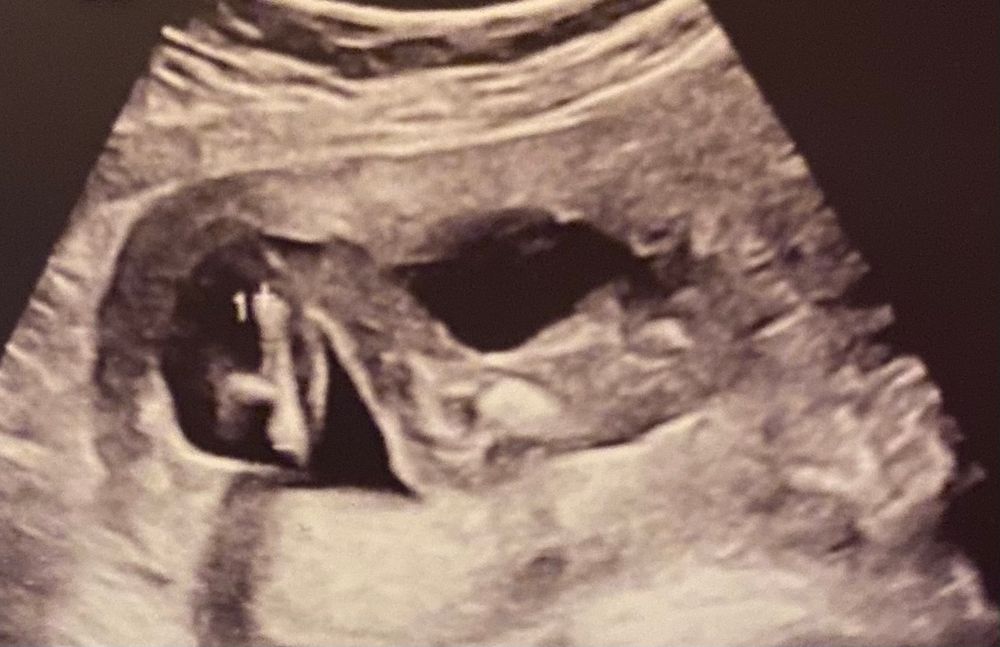

В 17 недель уже не половой бугорок,а сформированные половые органы. И где тут его видно?) Тут же положение тела такое,что как бы нога не просвечивается. По этому фото невозможно сказать пол.

Я если честно, не вижу тут бугорка вообще. Вижу только попу и ногу согнутую в колене. Бугорок спрятался за бедром)

Бугорок смотрят в 12 недель, а в 17 там уже конкретные мужские причиндалы видны. Более удачный ракурс вашему узисту не удался?

На снимке не видно, да и в 17 недель узисты обычно точно пол называют, если конечно, узист и аппарат нормальные

Если я верно вижу, то это часть тела, жопка и нога? Но тут ни мальчика, ни девочки. Все закрыто ногой, если это она.